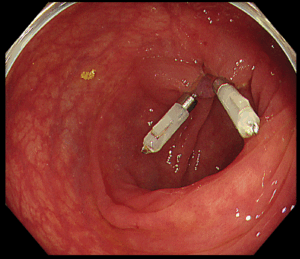

*EMR

大きめのポリープや凹みのあるポリープは粘膜の下に局注を行い電気で焼灼して切り取ります。傷口はクリップと呼ばれる器具で塞ぎます。